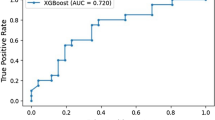

Sensitivity (Fig. 4) and specificity (Fig. 5) forest plots were produced. Performance receiver operating curve (ROC) is shown in Fig. 6. Forest plots depicting accuracy (S4), AUC (S5), F-1 (S6) and precision (S7) were made. These plots show the extreme heterogeneity between the included studies.